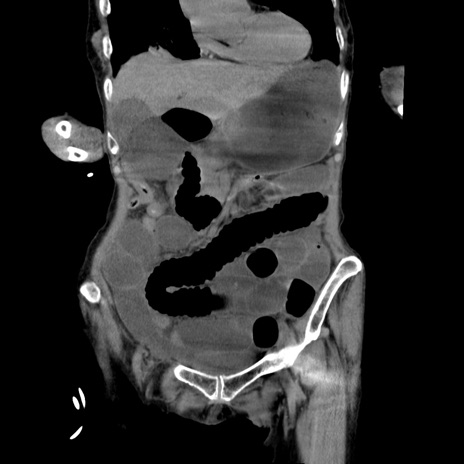

症例27(冠状断像)

【症例】80歳代女性

【主訴】嘔吐、腹痛

【現病歴】数時間前より嘔吐あり。心窩部痛出現し、徐々に右下腹痛あり。その後も数回嘔吐あり救急搬送となる。

【既往歴】左大腿骨頚部骨折手術

【身体所見】腹部は膨隆しているが軟らかく圧痛なし。腸雑音はやや亢進。

【データ】WBC 12000、CRP 19.05